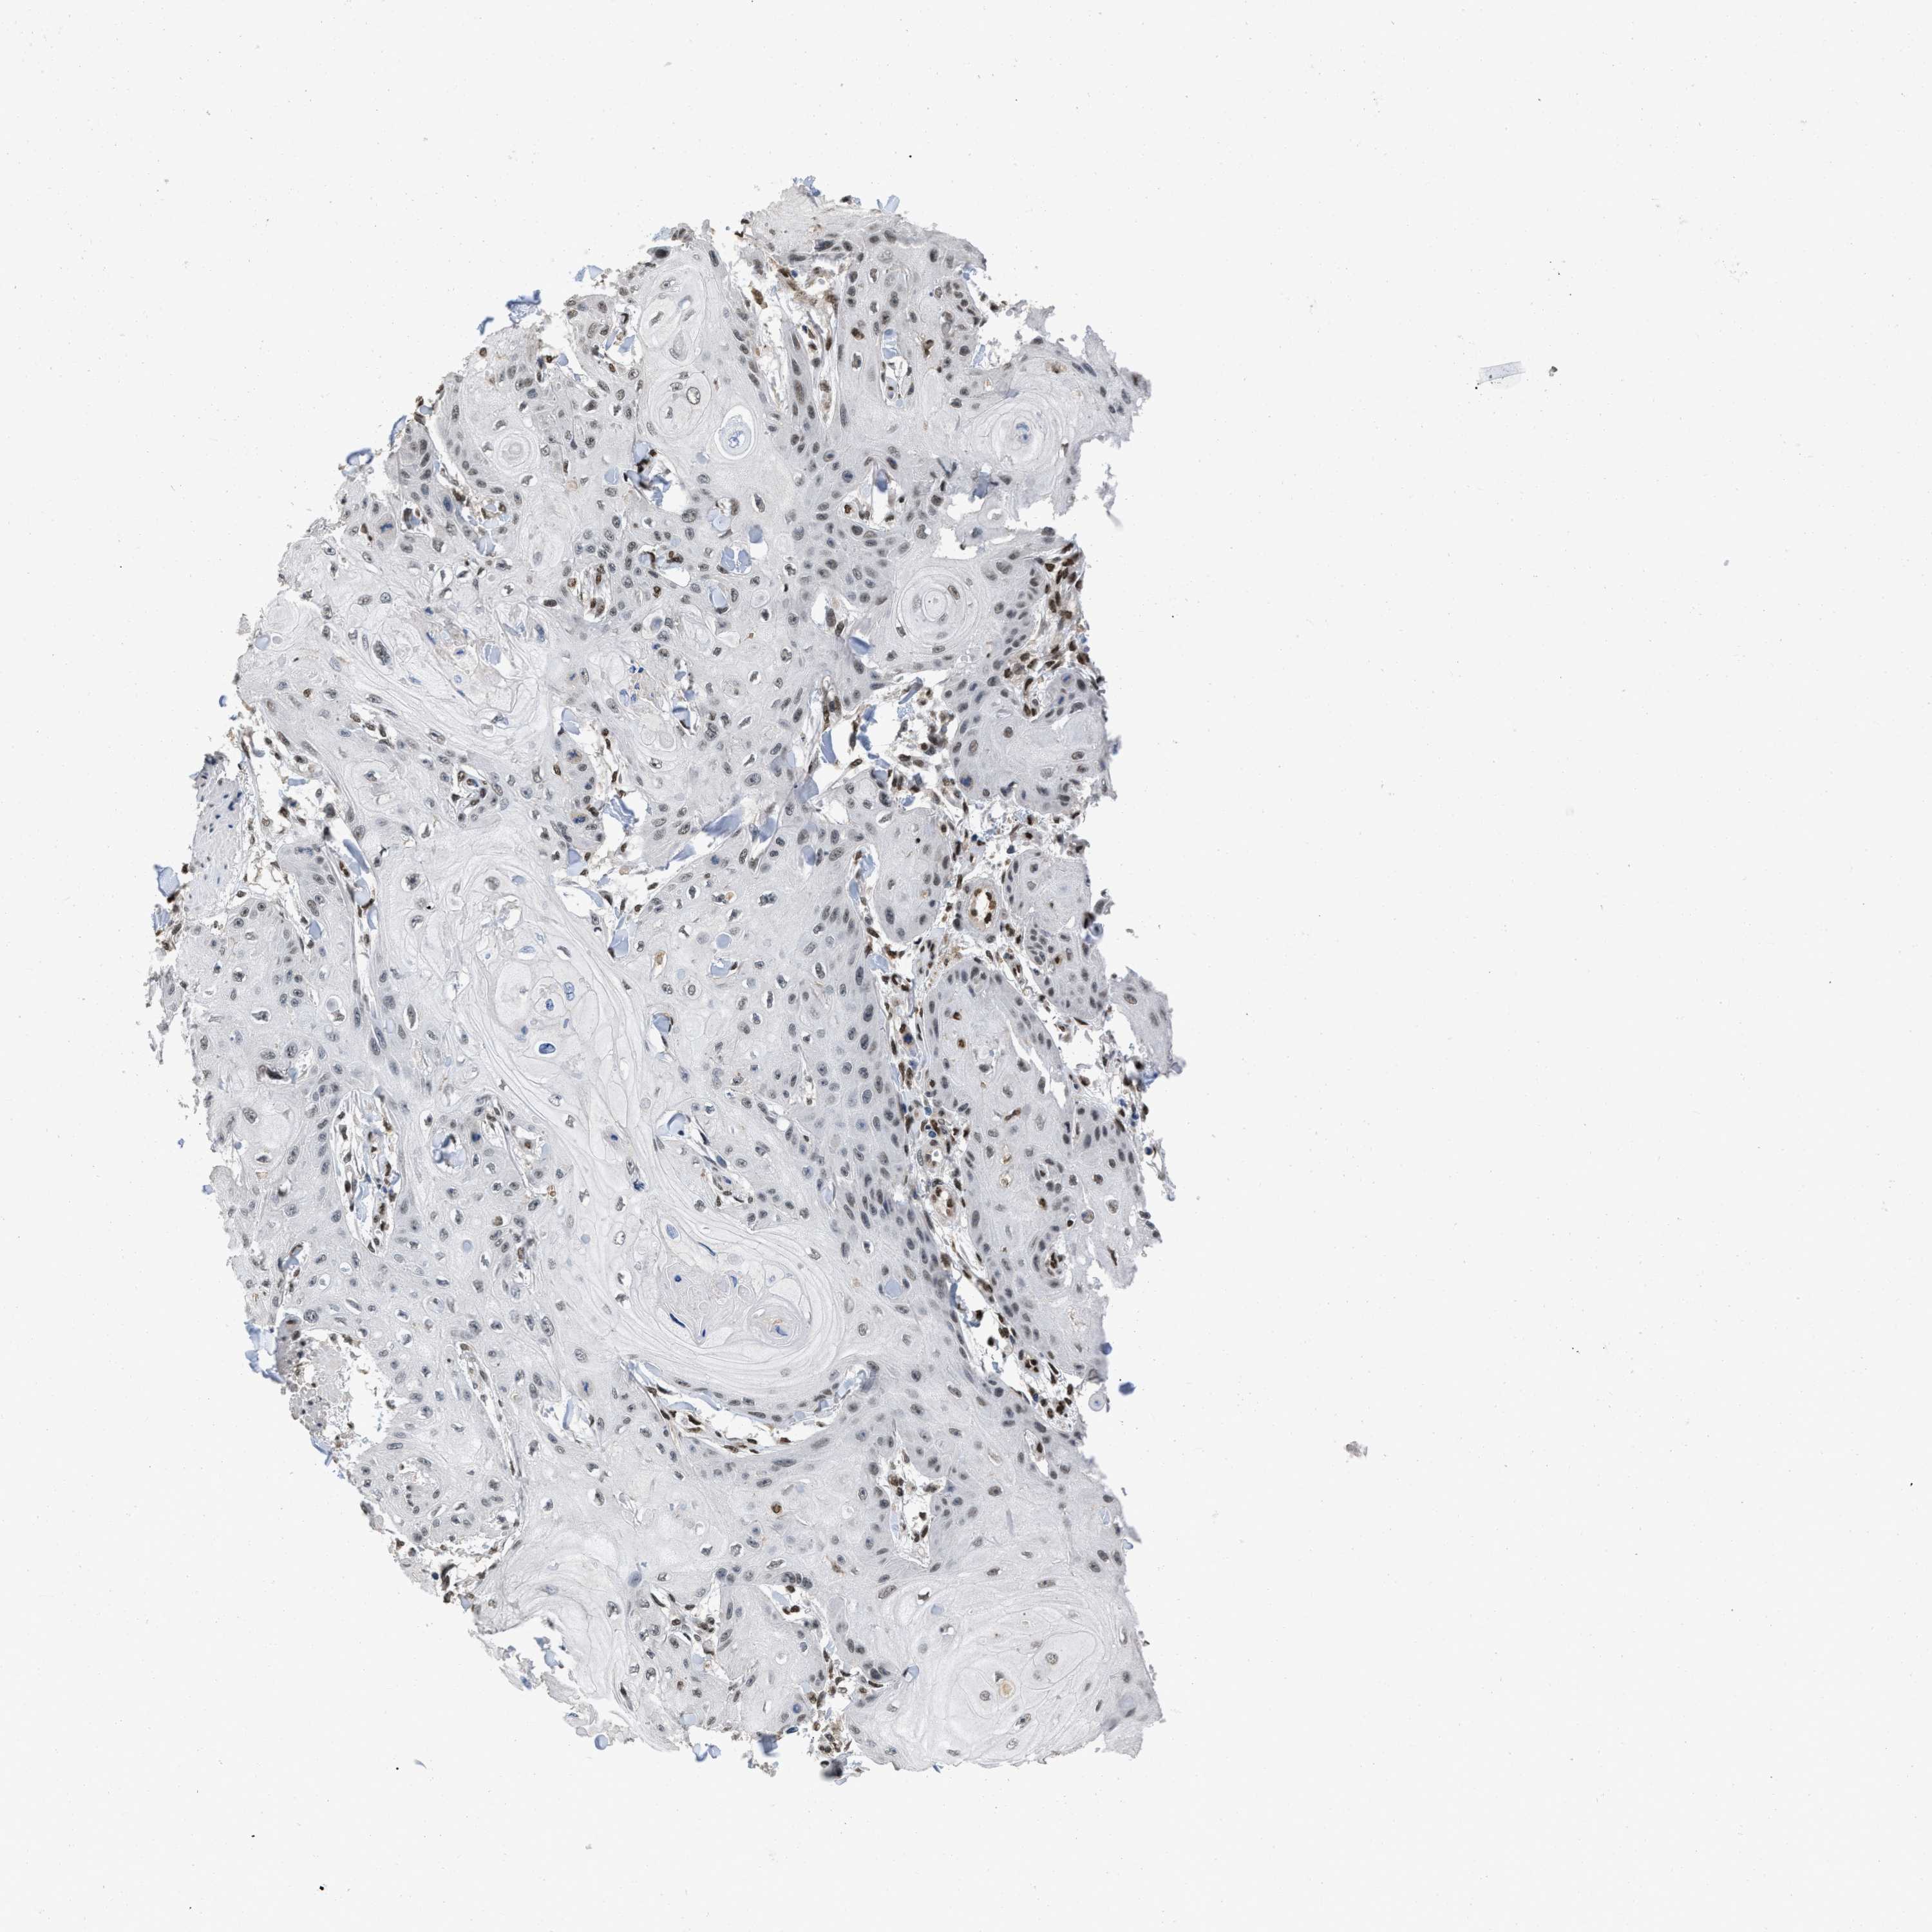

SKIN CANCER - Protein expressioni

A mouse-over function shows sample information and annotation data. Click on an image to view it in a full screen mode. Samples can be filtered based on level of antibody staining by selecting one or several of the following categories: high, medium, low and not detected. The assay and annotation is described here.

Each image is clickable and will lead to virtual microscopy that enables deeper exploration of all samples and also displays staining intensity scores, fraction scores and subcellular localization as well as patient and tissue information for each sample.

Antibody HPA019123

Antibody CAB022602

Staining

High

Medium

Low

Not detected

Intensity

Strong

Moderate

Weak

Negative

Quantity

>75%

75%-25%

<25%

None

Location

Nuclear

Cytoplasmic/membranous

Cytoplasmic/membranous,nuclear

Squamous cell carcinoma in situ, NOS

Squamous cell carcinoma, NOS

Squamous cell carcinoma, metastatic, NOS

Basal cell carcinoma